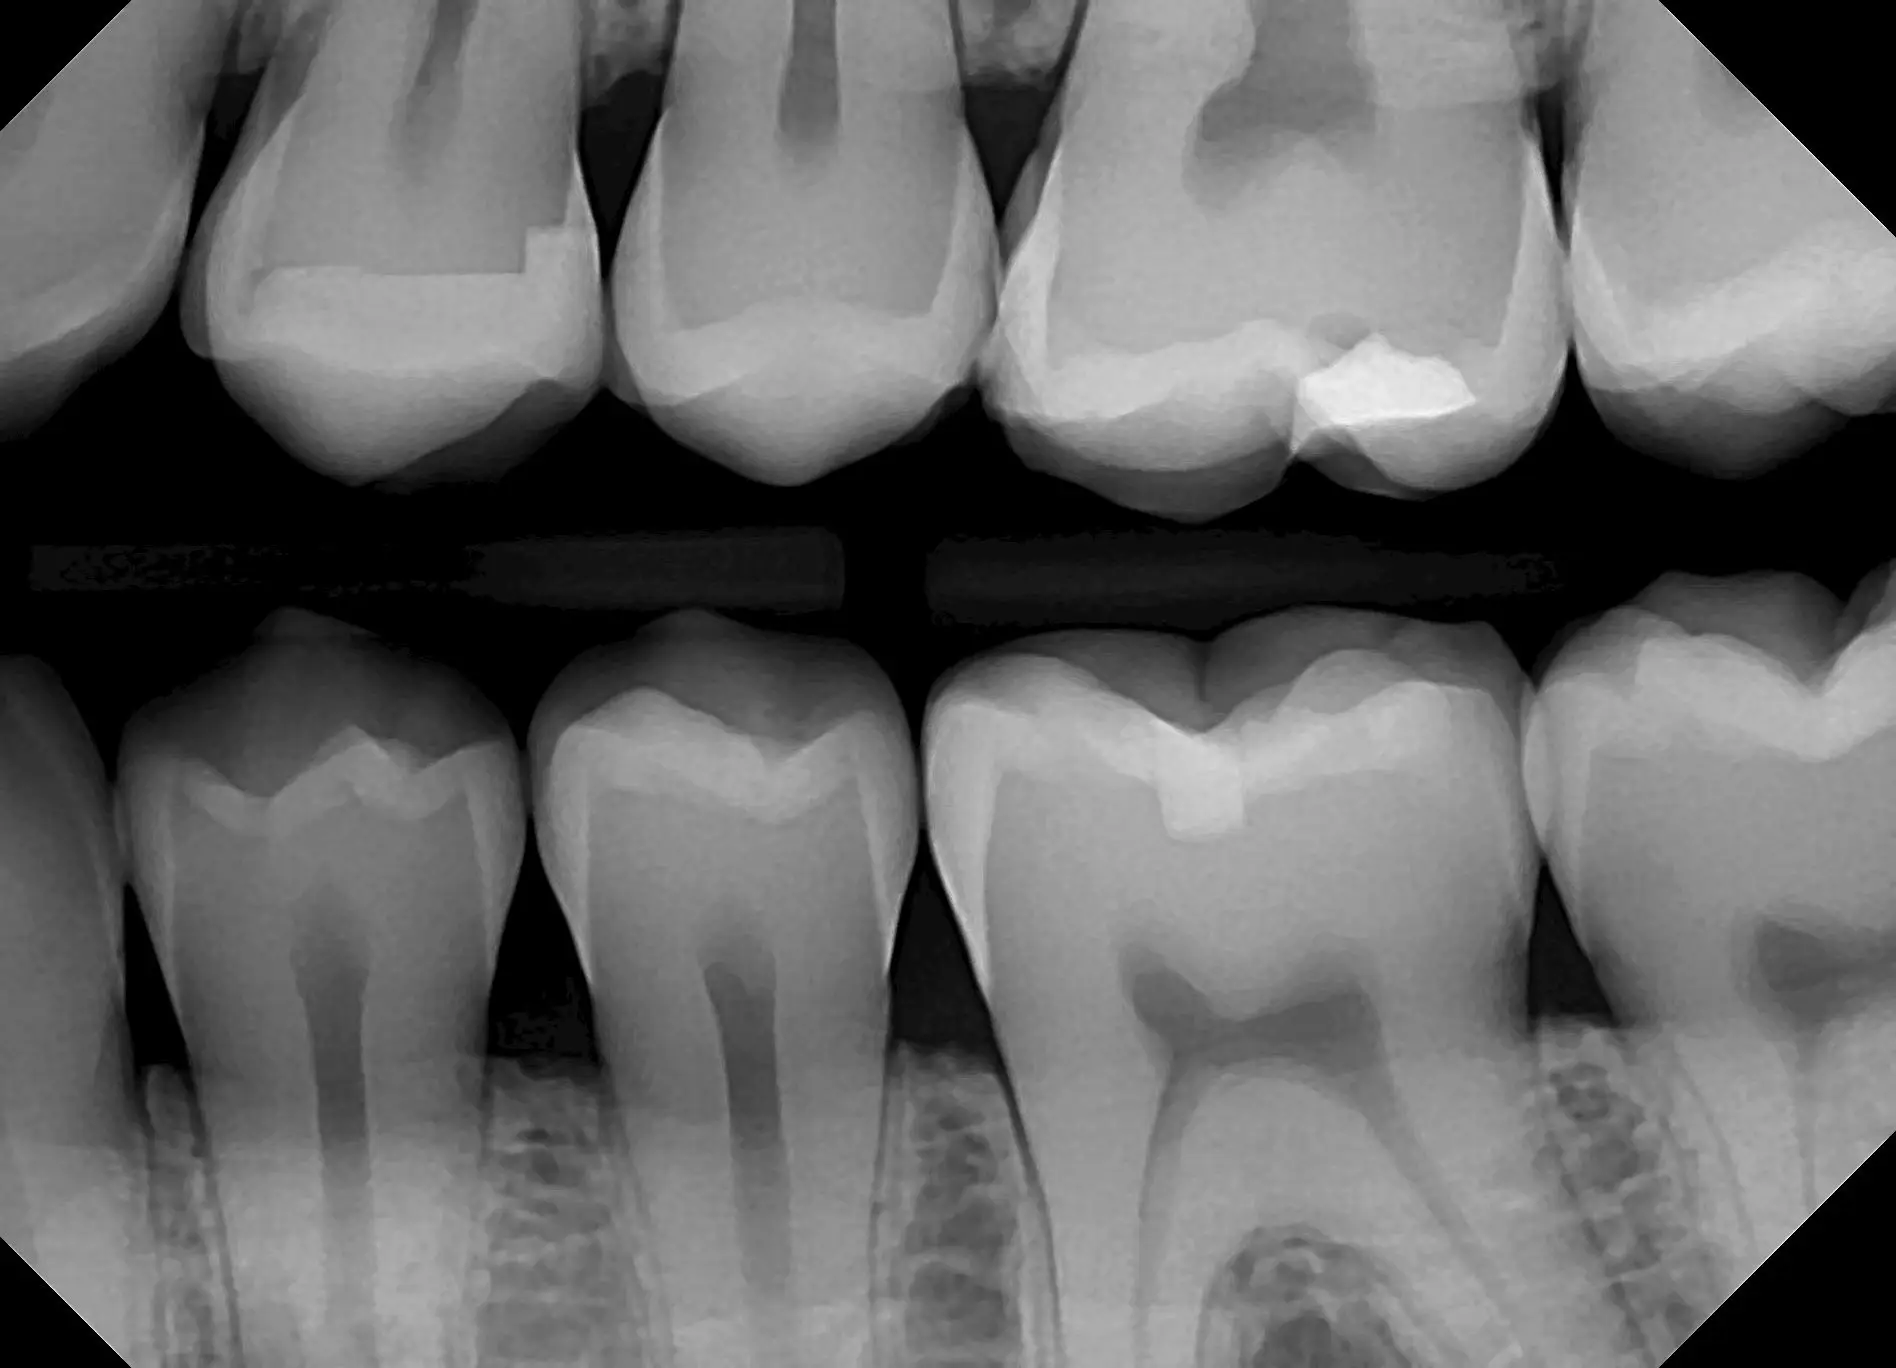

See for yourself the X-ray Gallery from the Dream Sensor!

Click any image in the x-ray gallery below to see the full version.

All images are taken with the DentiMax Dream Sensor and are compatible with the DentiMax Imaging Software and most other imaging software on the market.